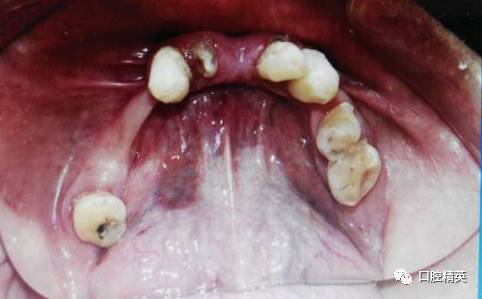

上颌旧义齿检查:张口说话咀嚼义齿脱位,无吸附力,上颌前牙过度唇倾,覆盖较深,颌平面低于上唇缘,微笑不露义齿,口角下垂,面部下1/3欠丰满。腭盖为金属基托,义齿后部未达腭小凹后2mm处。下颌金属支架义齿,33牙缺失。

下颌修补33义齿